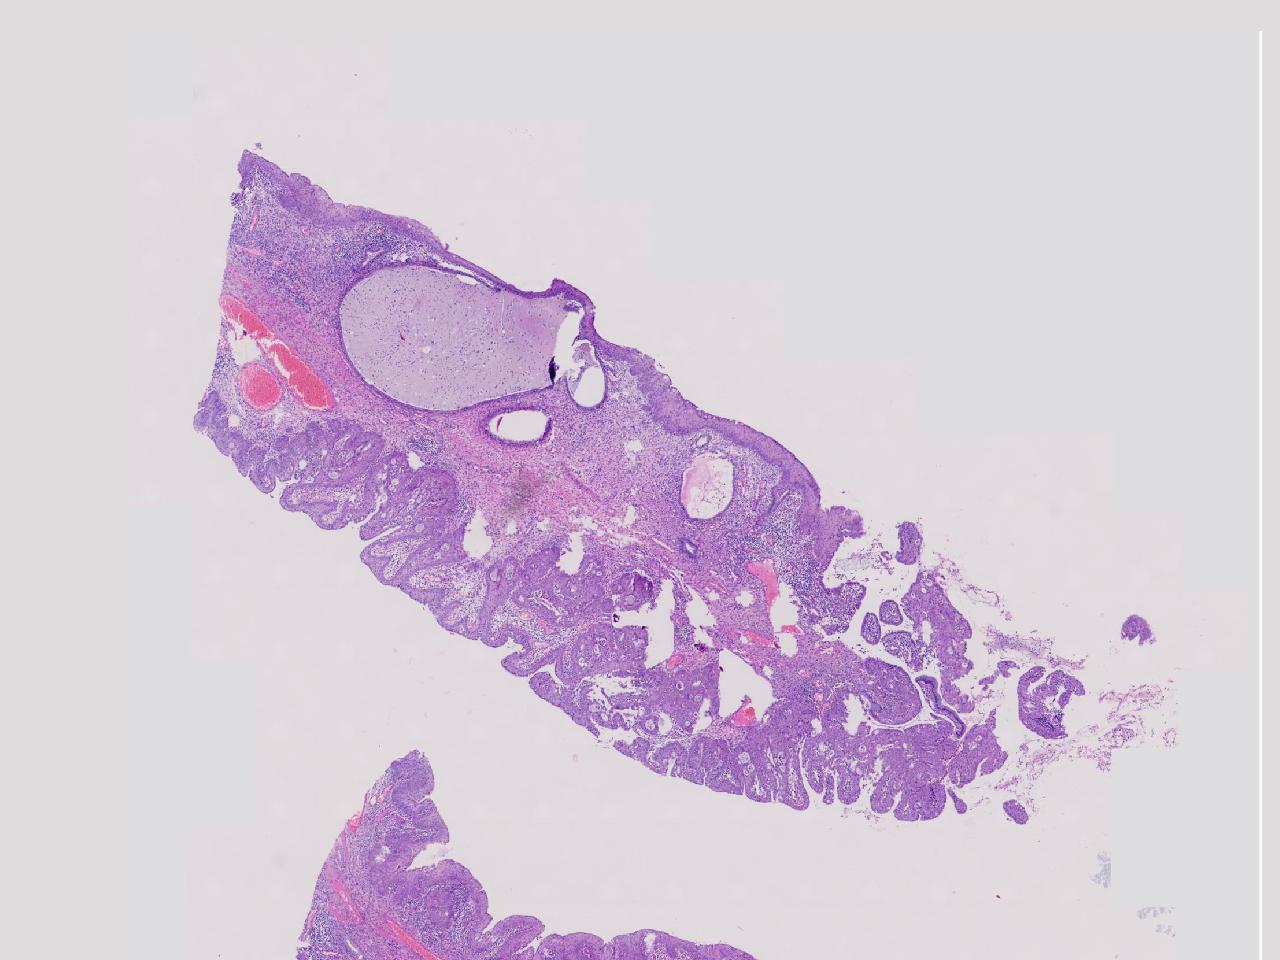

炎? 低级别?

性别年龄42岁临床诊断宫颈赘生物

一般病史女,42岁,妇检时发现宫颈赘生物,大小0.2cmx0.5cm

标本名称管状赘生物

大体所见灰白色不整形软组织2块,一个直径0.3厘米,一个直径0.2厘米。

炎症

低级别诊断需要有个尺子,这个尺子就是“似是而非为非”,这个连似是而非都达不到。

有非典型鳞化,建议HPV检测

慢性宫颈炎伴腺上皮鳞化。